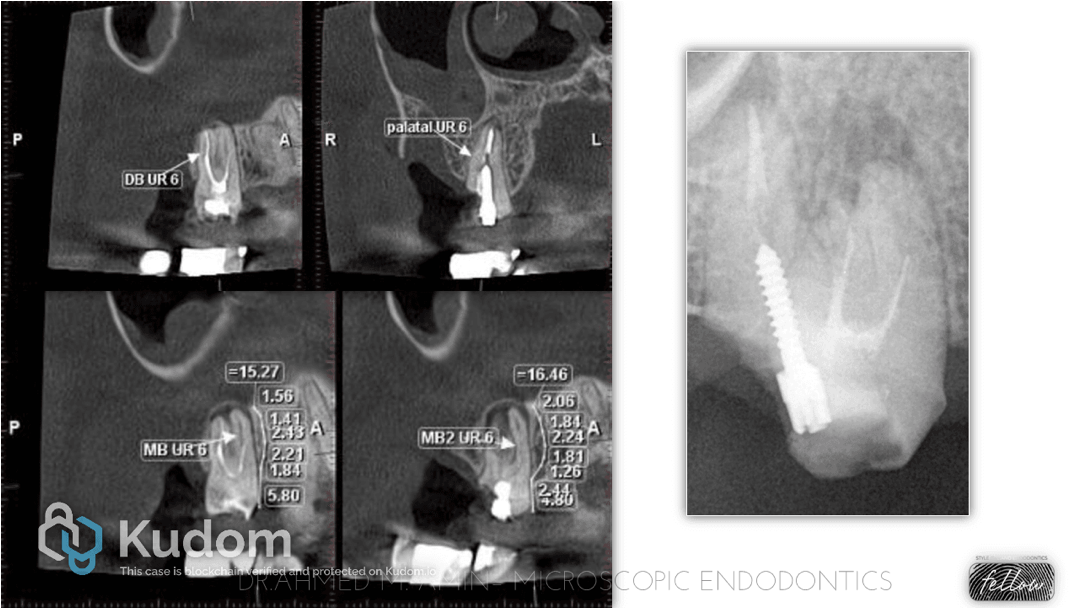

Selective root canal retreatment of an upper first molar: A 12 months CBCT-assessed outcome

Uncategorized

Selective root canal re-treatment is a novel approach which aim at treating the selected root/s showing apical pathology.

Thanks to the use of CBCT it is now possible to evaluate with high accuracy the status of a root filled tooth and plan the re-treatment strategy accordingly.

This approach has clear advantages in terms of preservation of tooth structure, reduction of iatrogenic errors and reduced operating time and costs.